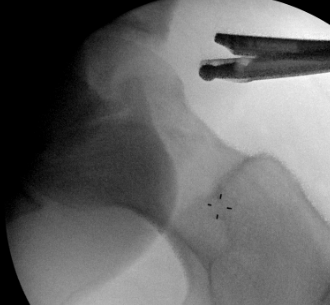

Mid Anterior portal

- stay lateral to line drawn down from ASIS to prevent NV injury

- aim for tip of camera on image intensifier

- judge anterior posterior using femoral head / acetabulum

- enter capsule between labrum and femoral head